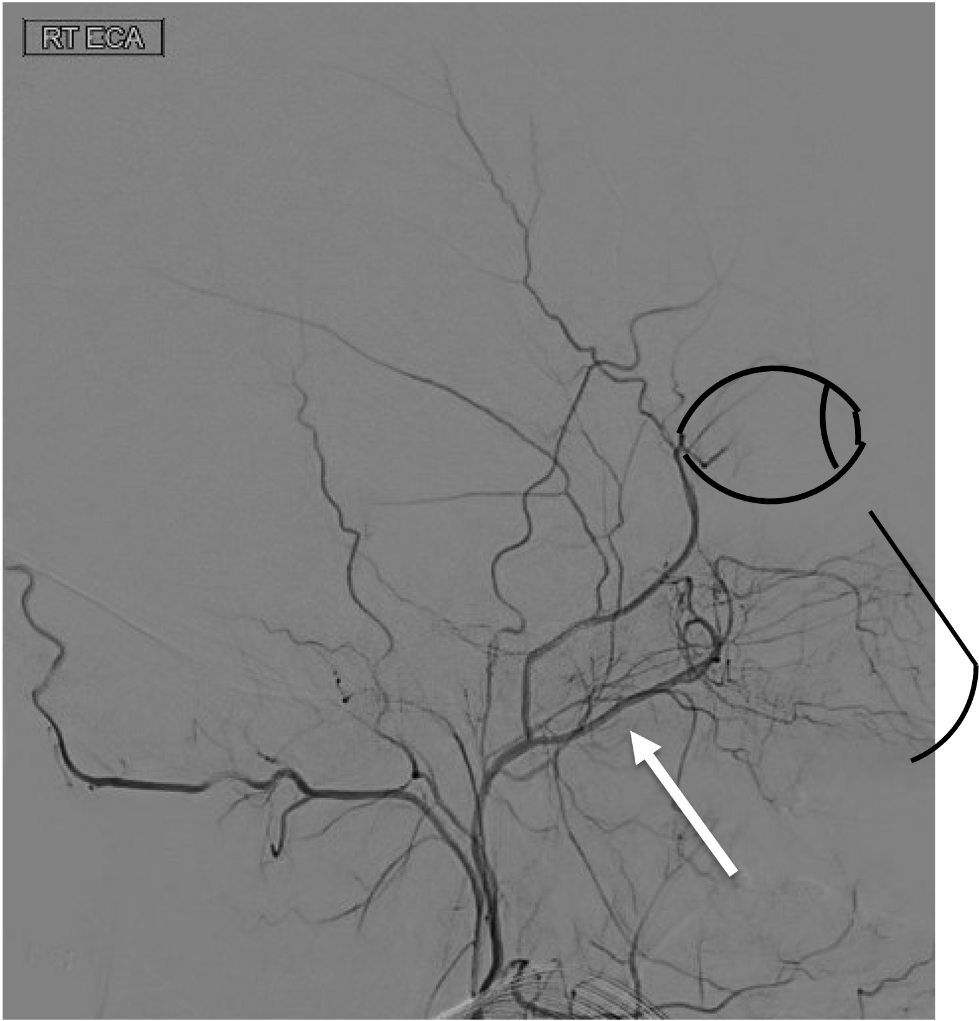

On this lateral view of the R ECA injection, name the following branch:

Internal maxillary artery